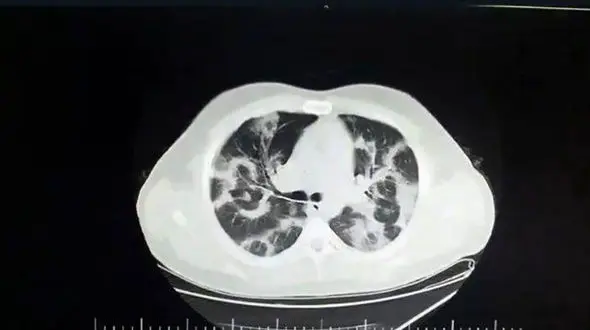

رکنا: بعد از چند ماه جهش هایی در کرونا به وجود آمد و سرعت انتقال و قدرت کشندگی آن افزایش یافت.

رکنا: رییس تیم واکنش سریع کووید_19 در کشور، ضمن تشریح وضعیت اپیدمی و همچنین گزارشهای مربوط به گردش ویروس جهش یافته در کشور، اظهار کرد: طغیان شدید اپیدمی و یا بروز پیک چهارم سرنوشت محتوم کشور نیست و…